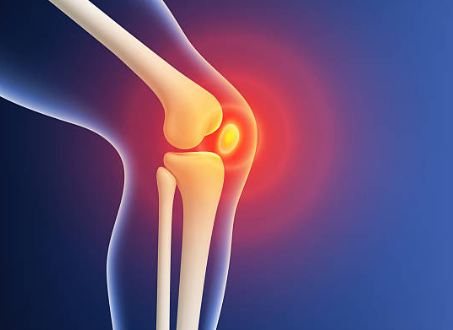

무릎에는 뼈가 서로 부딪히지 않도록 도와주는 “연골”이 있어요.

대표적으로 두 가지가 중요합니다.

첫째, 관절연골

무릎뼈 끝을 매끈하게 감싸서 마찰을 줄여주고 충격을 흡수해요.

둘째, 반월상연골(반달연골)

무릎 안쪽과 바깥쪽에 있는 반달 모양의 연골로, 체중이 한쪽에 쏠리지 않도록 분산해 주는 역할을 해요.

이 연골이 닳거나 찢어지거나 손상되면 무릎이 뻣뻣하고 아프고, 걷는 자세까지 달라지면서 다른 관절까지 무리가 가기 쉬워요.

연골은 혈관이 거의 없어서 “피가 통하면서 빨리 낫는 조직”이 아니에요. 그래서 작은 손상도 그냥 넘기지 말고, 초기에 관리해 줘야 회복이 훨씬 수월합니다.